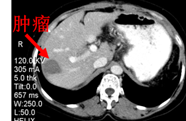

手术方案:选择性贲门周围血管离断术+脾切除术+右肝后叶占位活检+术中微波消融术

术中穿刺病理提示:(肝右叶)肝细胞癌

消融后(术后1月)CT图像: